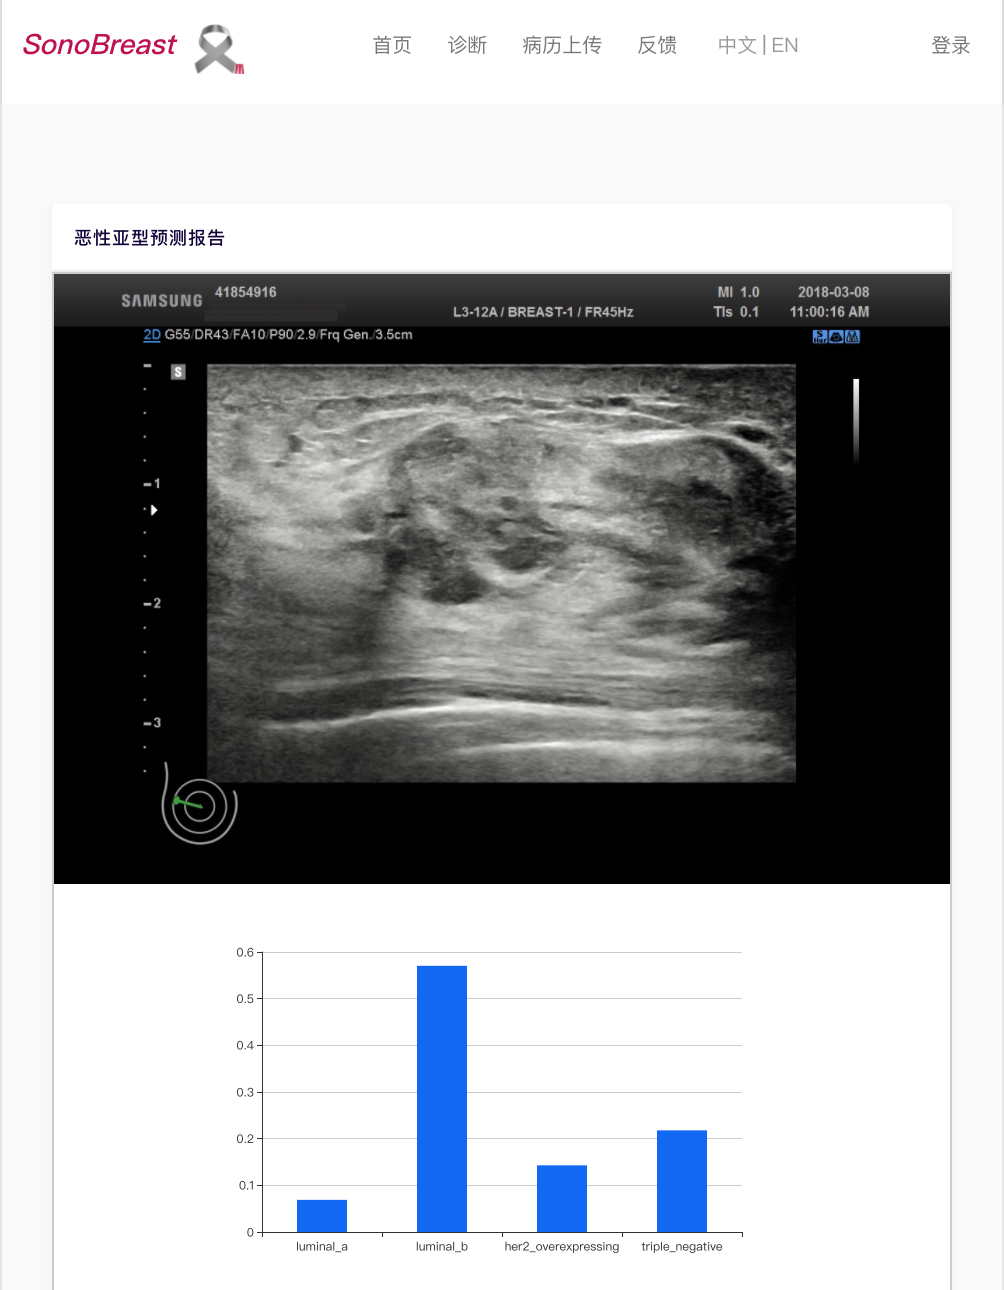

分子亚型 :该工具可预测乳癌性病变的分子亚型。对于患者病变的一组给定的超声图像(至少一个图像),将提供病变的预测分子亚型诊断以及置信度(每个亚型的概率)。

目前,研究团队已经发布了 web 应用程序,允许病人和医生使用该预测模型上传超声图像。用户可以上传一定数量的超声图像,然后根据需要选择超声筛查部分,在提交图像后,由模型计算预测结果,并用直方图显示模型图的置信度。